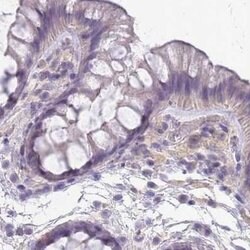

Invitrogen™ SLC8A2 Polyclonal Antibody

Brand: Invitrogen™ PA562250

| Immunohistochemistry (Paraffin) | |